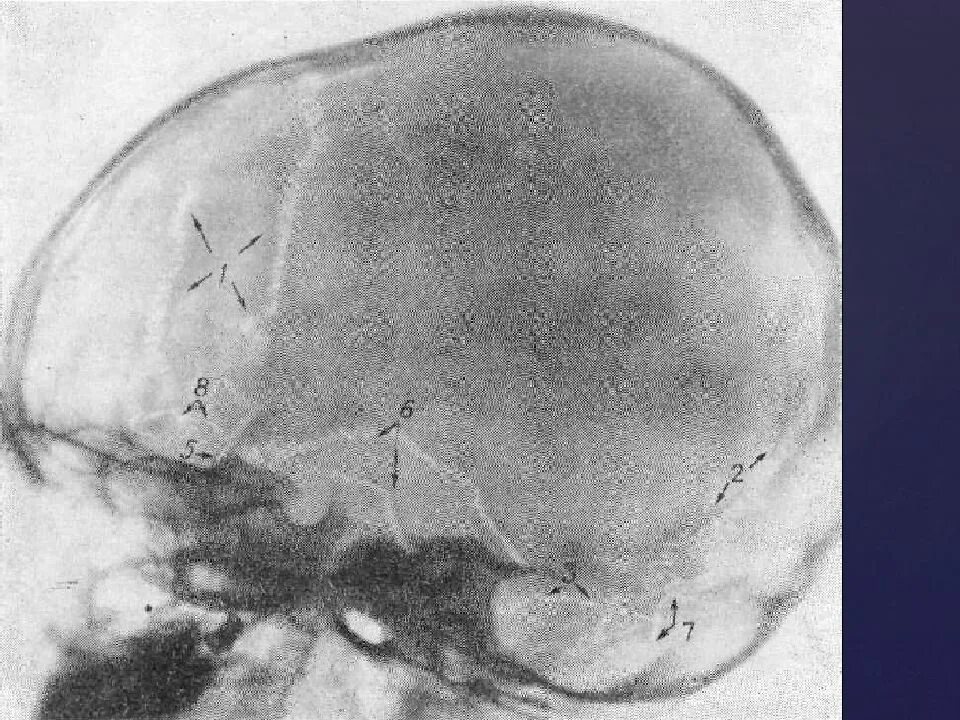

Обызвествление в проекции